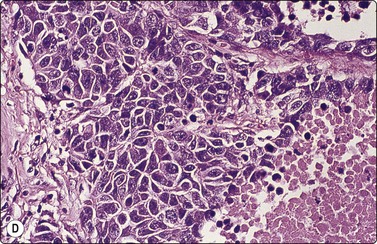

image image image

Fig. 8.28 High-grade neuroendocrine carcinoma; small cell carcinoma

(A, B) Smears showing ‘intermediate’ morphology. Loose aggregates of fragile cells with traumatization artifact and nuclear molding but some background cytoplasm (A, Pap, MP; B, H&E, HP). (C) Tissue section of resected peripheral stage 1 small cell carcinoma (H&E, HP).

image image image image image

Fig. 8.29 High-grade neuroendocrine carcinoma

Variable morphology including small cell and large cell patterns. (A) Low-power smear appearances of small cell carcinoma; (B) Higher-power examination shows some large cells with prominent nucleoli (A, H&E, LP; B, H&E, MP). (C,D) Tissue sections of resected peripheral stage 1 tumor showing areas of geographic necrosis and a predominance of large cells with prominent nucleoli (C, tissue section, H&E, LP, Inset, HP; D, tissue section, H&E, HP). (E) Positive immunostaining for chromogranin in resected specimen (E, tissue section, IPOX, HP).